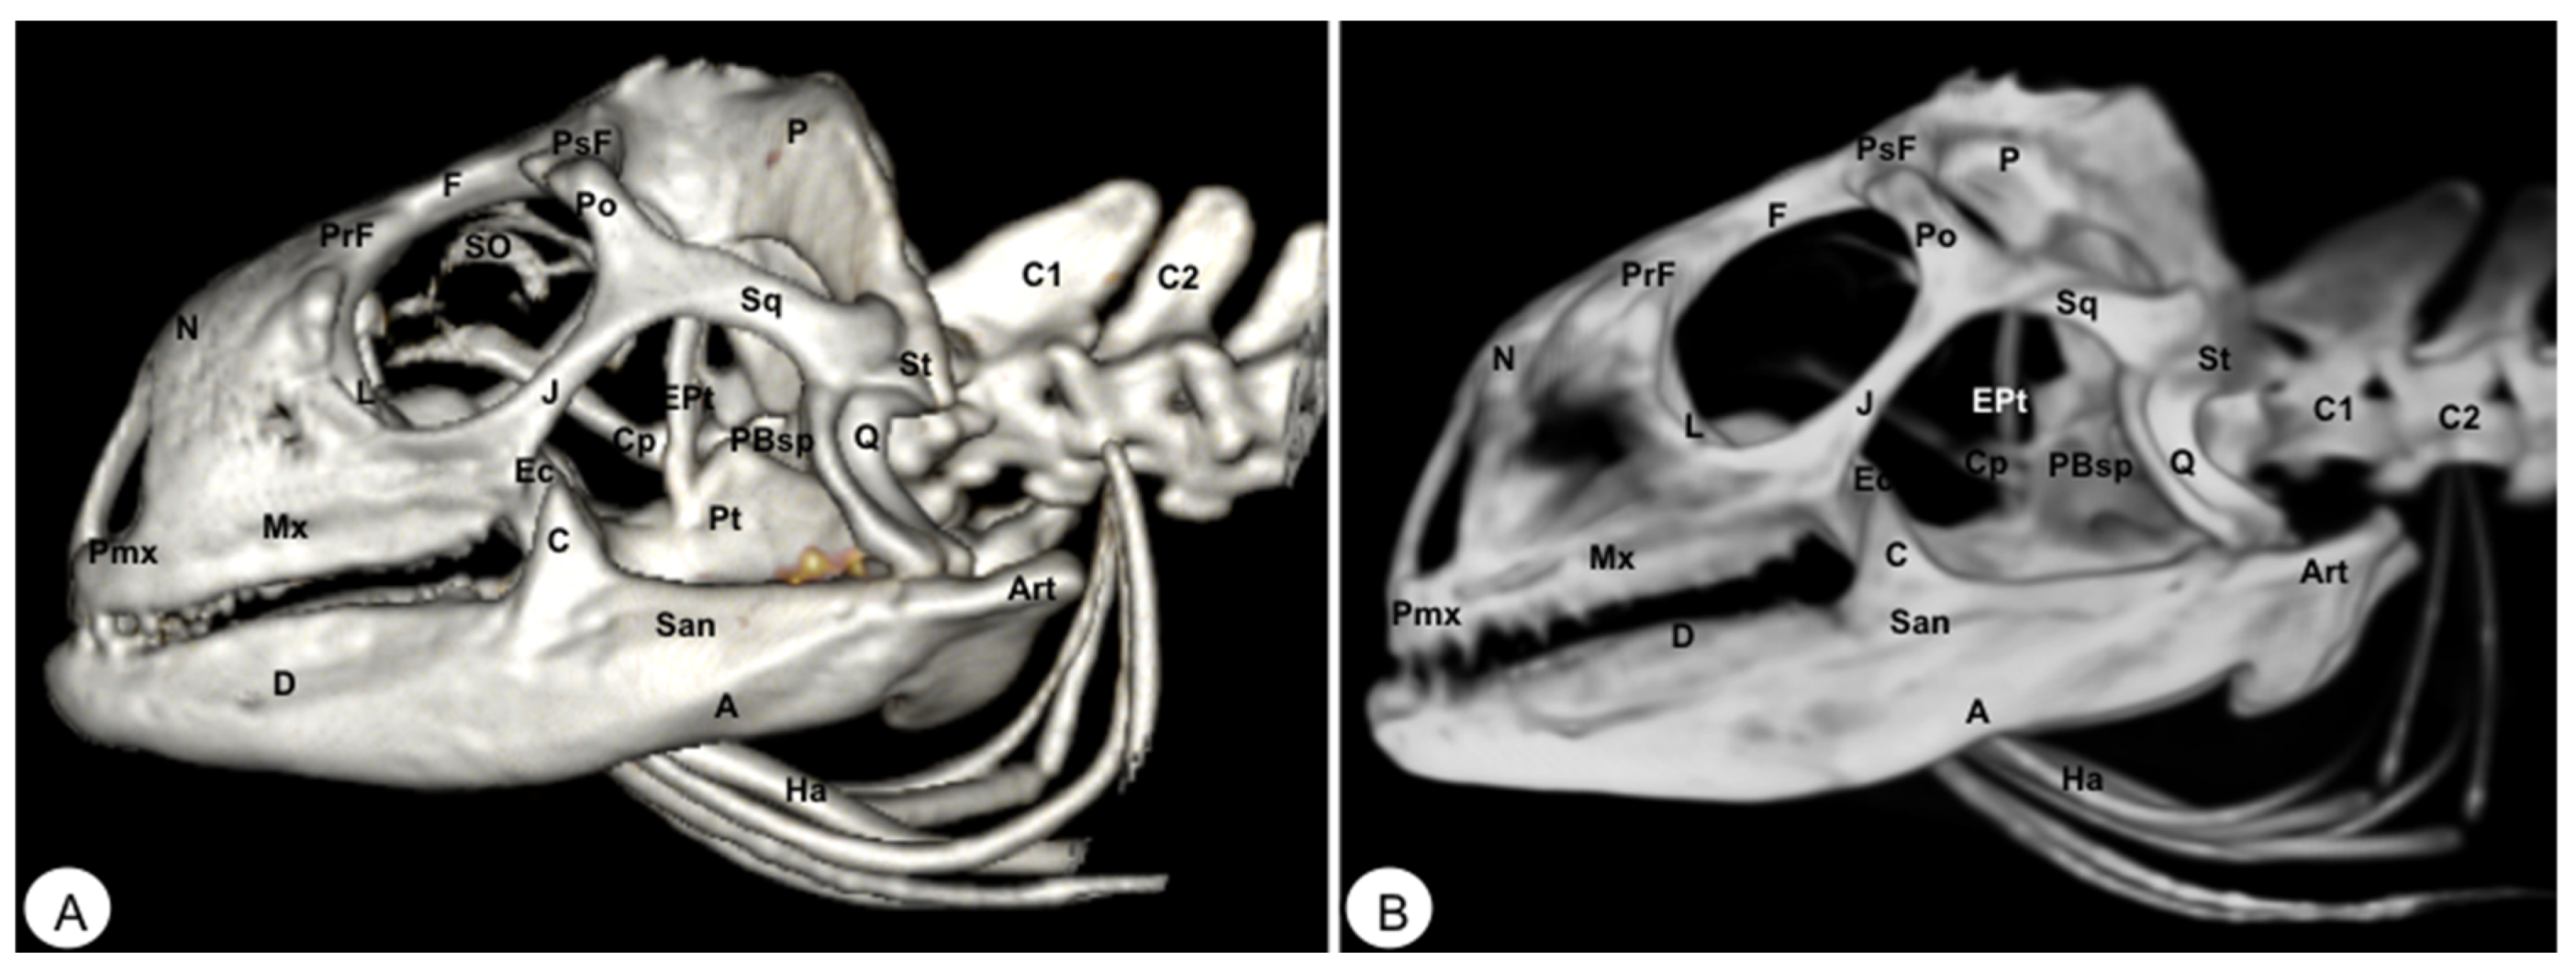

Figure 8. Head of Iguana iguana. (A) Lateral VR image. (B) Lateral MIP image. Pmx: Premaxillary. Mx: Maxillary bone. N: Nasal. PrF: Prefrontal. L: Lacrimal. F: Frontal. PsF: Postfrontal. Po: Postorbital. SO: Scleral ossifications. J: Jugal. Q: Quadrate. Sq: Squamosal. Ec: Ectopterygoid. Pt: Pterygoid. EPt: Epipterygoid. Cp: Cultriform process. PBsp: Parabasisphenoid. P: Parietal. St: Supratemporal. D: Dentary. A: Angular. San: Surangular. Art: Articular. C: Coronoid. Ha: Hyoid apparatus. C1: First cervical vertebra. C2: Second cervical vertebra.

The maxilla is a pair of bones that meet each other at the midline under the palatal bones. Therefore, it is located along the lateral edge of the vomer and palatine bones, surrounding the ventral border of the eye orbit (Figure 2). In the rostral and lateral MIP images of the loggerhead turtle (Figure 2B and Figure 3B), this bone meets rostromedially with the premaxillary bone, ventromedially with the vomer and palatine bones, and caudally along the ventral border of the jugal bone (Figure 2 and Figure 3A). Concerning the iguana, this bone arises lateral and ventral to the nasal bone on each side of the skull, contacting it rostrally with the premaxilla (Figure 7 and Figure 8), the lacrimal and nasal bones dorsally, and the jugal caudolaterally (Figure 8).

3.1.3. NASAL (Os Nasale)

In the iguana, the nasal bones are broad and slightly convex dorsally. The VR and MIP images showed the nasal bone junction in the mid-sagittal plane and how the nasal bones were distinctly longer than wide (Figure 8), contacting with the neighboring bones such as the lacrimal bone caudolaterally, the maxilla rostrolaterally, the prefrontal bone caudodorsolaterally, and the frontal bone caudodorsomedially (Figure 7, Figure 8 and Figure 10).

In these species, the frontal bone shows a flat shape and lies in the anterior part of the skull (Figure 2, Figure 3, Figure 5, Figure 7, Figure 8 and Figure 10). The rostral VR turtle reconstruction showed a clear view of the prefrontal and frontal bone junctions (caudomedially). Therefore, the frontal bone contacts the prefrontal bone (rostrally), the postorbital bone (laterally), and the parietal bone (caudally) (Figure 2, Figure 3 and Figure 5). As our animals were adults, we could observe how this bone was excluded from the orbit. The VR and MIP images of the green iguana showed that the prefrontal bone contacts rostromedially with the nasal bone, rostrolaterally with the lacrimal bone (paired small bones located in the lateral region of the orbit observed only in the iguana), and caudomedially with the frontal bone (Figure 7, Figure 8 and Figure 10). The frontal bone is broad and forms a major component of the skull roof, contributing to the dorsal border of the orbit. It meets the prefrontal bone rostrolaterally, the postfrontal bone caudolaterally, and the parietal bone caudally (Figure 7, Figure 8 and Figure 10). Laterally, it is differentiated from the postorbital by the postfrontal bone.

3.1.7. POSTFRONTAL-POSTORBITAL

The postorbital bone forms part of the temporal arch, and most of the posterior margin of the orbit. This bone contacts dorsocaudally with the parietal bone, anterodorsally with the prefrontal bone, and ventrally with the jugal bone (Figure 2, Figure 3 and Figure 5), excluding, therefore, the frontal bone from the orbit. It reaches the squamosal caudally (Figure 3A and Figure 5) and contacts the prefrontal bone rostrally (Figure 2A, Figure 3A and Figure 5). Regarding the iguana, those bones were broad and could be well identified in VR and MIP rostral, dorsal, and lateral images as two different bones. The postfrontal bone arises in the caudodorsal part of the orbit and meets the frontal bone (rostromedially), the parietal bone (caudomedially), and the postorbital bone (caudolaterally) (Figure 7, Figure 8 and Figure 10). In contrast, the postorbital bone meets the postfrontal bone dorsally, the squamosal bone caudolaterally, and the jugal bone rostrolaterally (Figure 8 and Figure 10).

3.1.8. PARIETAL (Os Parietale)

3.1.9. JUGAL (Os Jugale)

The jugal bone is one of the main elements of the zygomatic arch under the orbit in both species, showing an “L” shaped configuration in VR and MIP lateral images. Rostral and lateral VR images were quite useful in distinguishing the arrangement of this bone at the caudoventral border of the orbit. Moreover, the rostral, lateral, and ventral VR and MIP images of the turtle show how this bone contacts dorsocaudally with the postorbital bone, rostrally with the maxilla, and posteriorly with the quadratojugal bone (resulting in the zygomatic arch). In contrast, the jugal bone in the iguana is observed as a curved bone (seen by rostral, lateral, and dorsal VR and MIP images) that runs forward along the orbital border to make contact with the lacrimal (dorsally) and maxillary bones rostrally. Caudodorsally, it angles slightly upwards to meet with the postorbital and the squamosal bones. Ventrally, it contacts the ectopterygoid bone.

3.1.10. QUADRATE (Os Quadratum)

3.1.12. SQUAMOSAL (Os Squamosum)

3.1.13. PTERYGOID (Os Pterygoideum)

This flat bone lies between the vomer and palatine bones (rostrally) and the parabasisphenoid (caudally) bones (Figure 4) in the loggerhead turtle, reaching the quadrate bone caudally and the palatine bone rostrally (Figure 3B and Figure 4). Interestingly, this bone is fussed with the turtle. In contrast, the iguana was completely separated (Figure 9B,C). This bone has a dorsal projection called the epipterygoid that contacts the parietal bone (Figure 3B and Figure 8) in both species. Nonetheless, we observed that the iguana showed two rostral projections called ectopterygoid bones (Figure 8 and Figure 9), which contacted rostromedially with the pterygoid palatine process (Figure 9B,C), and laterally, it contacts with the jugal and the maxillary bones (Figure 8 and Figure 10).

3.1.14. EPIPTERYGOID

The epipterygoid bone in the turtle consists of a tubular-shaped bone that extends vertically from the pterygoid bone and contacts the parietal (Figure 3B). A similar configuration was observed in the iguana, where this bone is a thin road that touches dorsally the parietal bone (Figure 8).

The parabasisphenoid is a roughly trapezoidal bone located between the pterygoid (rostrally), and the basioccipital (caudally) bones (Figure 4, Figure 5B, Figure 6, Figure 8 and Figure 9). This bone forms part of the ventral surface of the skull and has two lateral processes that contact the pterygoid bone, called basipterygoid processes, which are short and thick, and well identified in the iguana (Figure 9C). Between these processes, we observe a thin and tubular structure named the cultriform process (Figure 8 and Figure 9), which is well developed compared to other iguana species. This latter also shows two alar processes in the laterocaudal direction (Figure 9B,C).

The basioccipital bone in the turtle is a rectangular-shaped bone located in the posterior half of the planum basale, contacting the basisphenoid (rostrally) and exoccipital (caudally) bones, forming part of the floor of the cavum cranii (Figure 3B, Figure 4 and Figure 6). In the iguana, it roughly reaches the parabasisphenoid and caudally the occipital bone (Figure 11), forming part of the occipital condyle.

3.3.1. DENTARY (Os Dentale)

The dentary bone is the major bone of the mandible in both species. Its lateral surface appears pierced by small foramina, where mandibular nerve branches and blood vessels run. In the iguana, it carries pleurodont teeth. This bone was better visualized in the rostral, lateral, and ventral VR and MIP images. Either in the turtle or the iguana, it joins the coronoid and the surangular caudodorsally (Figure 2, Figure 3, Figure 4, Figure 8 and Figure 9), the angular caudoventrally (Figure 3, Figure 4, Figure 8 and Figure 9), and the splenial bone medially.

3.3.2. ANGULAR (Os Angulare)

The angular bone is a laminar bone located in the caudal aspect of the mandible from the rostromedial to the caudolateral aspect, forming the ventrocaudal margin of the mandible. This bone was well visualized in the lateral MIP and VR images of these species (Figure 3 and Figure 8). The connections of the angular bone in both species are the dentary bone rostrally, the splenial and prearticular bones dorsomedially, and the articular bone in the caudal direction.

3.3.3. SURANGULAR (Os Surangulare)

The surangular is a widely flat bone located below the coronoid along the dorsal border of the mandible and forming most of the caudolateral surface of the mandible. In both species, it is located posteriorly and slightly dorsal to the dentary, connected to the coronoid rostrodorsally, to the angular bone caudoventrally, and to the articular bone medially (Figure 3 and Figure 8).

3.3.4. CORONOID (Os Coronoideum)

The coronoid is a broadly triangular bony structure located approximately medial to each branch on the caudodorsal aspect of the mandible. This process is the highest part of the mandible in both species. This bone was better visualized in the lateral MIP view of the iguana than in the turtle, where we could distinguish how the coronoid tends to be slightly higher and more dorsally pointed than in the loggerhead turtle. Both species have the same configuration where the coronoid meets the dentary rostrolaterally, the surangular caudolaterally, the articular caudoventromedially, and the splenial bone ventromedially (Figure 3B, Figure 7 and Figure 8).

3.3.6. ARTICULAR (Os Articulare)

The articular bone is an irregularly block-shaped bone found at the caudal edge of the mandible in the turtle and the iguana. It was observed using both VR and MIP techniques (Figure 3, Figure 6, Figure 7, Figure 8, Figure 9, Figure 10 and Figure 11) and had the same configuration in both species. Thus, it joins with the surangular laterally and the angular ventrally, forming the retroarticular process, and dorsally with the coronoid bone.

3.3.7. HYOID APPARATUS (Os Hyoideum)

The hyoid apparatus is located in the intermandibular space. It provides support to the tongue, pharynx, as well as floor of the mouth. This apparatus consists of a pentagonal piece, which has three structures: a central (basihyal) structure, an anterior process, and two caudolateral processes (Figure 3A, Figure 4, Figure 5, Figure 6A, Figure 8, Figure 9, Figure 10A and Figure 11).